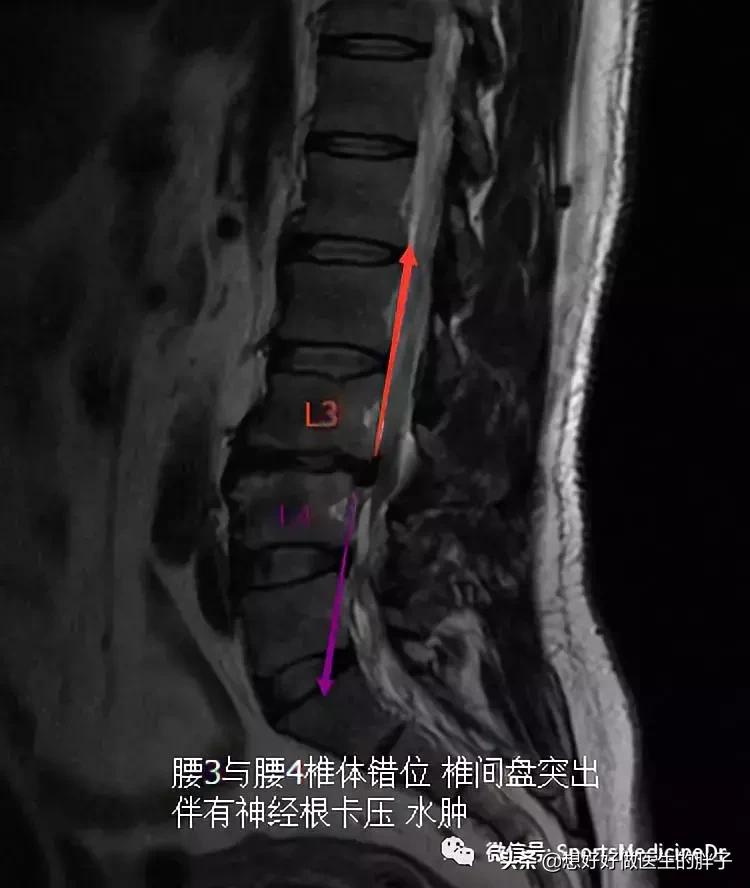

开始今天的文章之前,想请大家看看一个我最近患者的几张核磁片子,当这个患者进入诊室的时候,我的第一印象是这个人身材真好,四十多岁的年纪,虎背熊腰的,特别健壮!但是他表情异常痛苦,走路的时候一瘸一拐的,当时我就觉得这个人可能是伤到腰了。果不其然,他的主诉确实就是腰痛,而且已经三个月了,腰痛越来越重,近几日更是开始出现了明显的下肢疼痛,步行超过200米就要休息一下。鉴于这个患者出现了明显的椎管狭窄和神经卡压的症状,给与其检查了核磁,结果如下,(说句实话,看到他的核磁我是比较惊讶的):

这是典型的腰椎间盘突出、椎体轻度滑脱并伴有椎管狭窄的核磁表现,但是一般腰突的患者最常见的椎间盘突出节段在腰4-5或者腰5-骶1节段,为什么这个患者出现在腰3-4节段呢?而且这个患者的腰3-4间隙明显的出现了过度的骨质增生,完全不像是40岁患者的核磁表现。